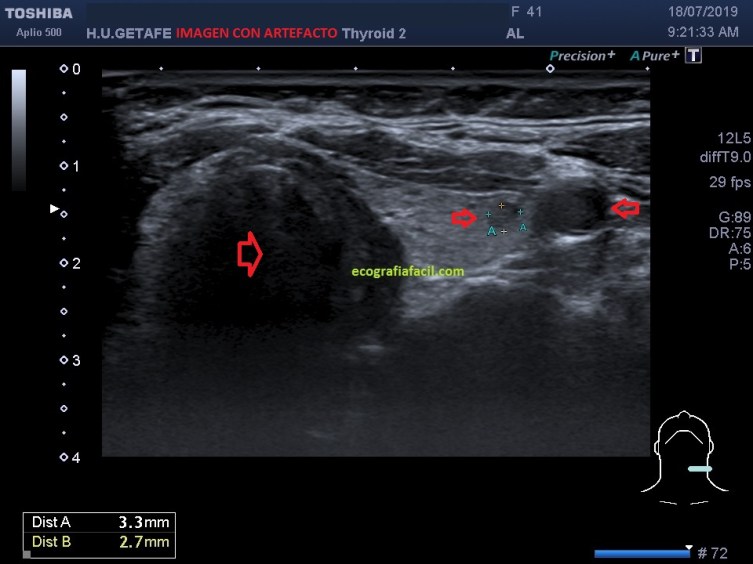

¿Pero cómo este artefacto degrada la imagen?, como una imagen vale más que mil palabras, te pongo dos imágenes de un corte del lóbulo tiroideo izquierdo, donde encontramos un nódulo pequeño. Observa y sobre todo presta atención a las flechas rojas.Son zonas de conflicto.

De los puntos de conflicto, principalmente, notamos el artefacto en dos, el nódulo y la arteria carótida izquierda, «manchada», más ecogénica de lo normal, (fig 1) cuando debería verse anecoica como en la figura 2. Sí, lo sé es muy sutil, pero es importante que la degradación de la imagen por pequeña que sea puede variar la fiabilidad diagnóstica, en este caso el nódulo de la figura 1 es menos nítido que el de la figura 2.

Of the points of conflict, mainly, we noticed the artifact in two, the nodule and the left carotid artery, «stained», more echogenic than normal, (fig1) when it should look anechoic as in figure 2. Yes, I know it is very subtle, but it is important that the degradation of the image however small can vary the diagnostic reliability, in this case the nodule of figure 1 is less clear than that of figure 2.